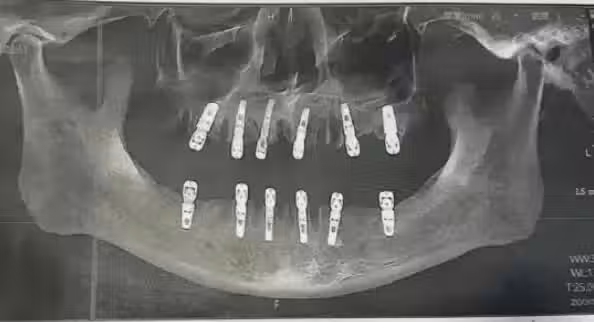

一次拔牙23顆!男子頻喊疼「13天後心臟驟停」身亡 女兒悲慟控訴「醫院講的不一樣」:多做1事

黃先生結束植牙手術後,一直感覺牙齒疼痛不止,在術後13天因心臟驟停死亡,噩耗來得措手不及,黃先生的女兒悲痛表示: 「沒想到我爸走得那麼快,給他買的新車都沒來得及開......」更控訴動手術的德維口腔醫院,手術同意書上寫的與工作人員介紹的注意事項不符!

圖/翻攝自 微博